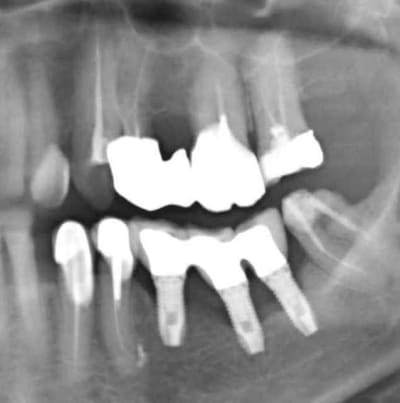

Grossière erreur lors des sutures et exposition de l'os et des implants, malgré tout on continue car belle gencive kératinisée après cicatrisation de ce bordel et résultat au bout de 2 ans ... (entre temps 38 a été virée)

en ce qui concerne ces micro-spires, tekka, à la demande d'utilisateurs ayant constaté des cratérisations à ce niveau, propose le progress sans les microspires:

http://www.tekka.eu/tekka/resource/filecenter/document/042-000010-000/00df-progress-fr-ed-1-09-nouveaute-apercu.pdf